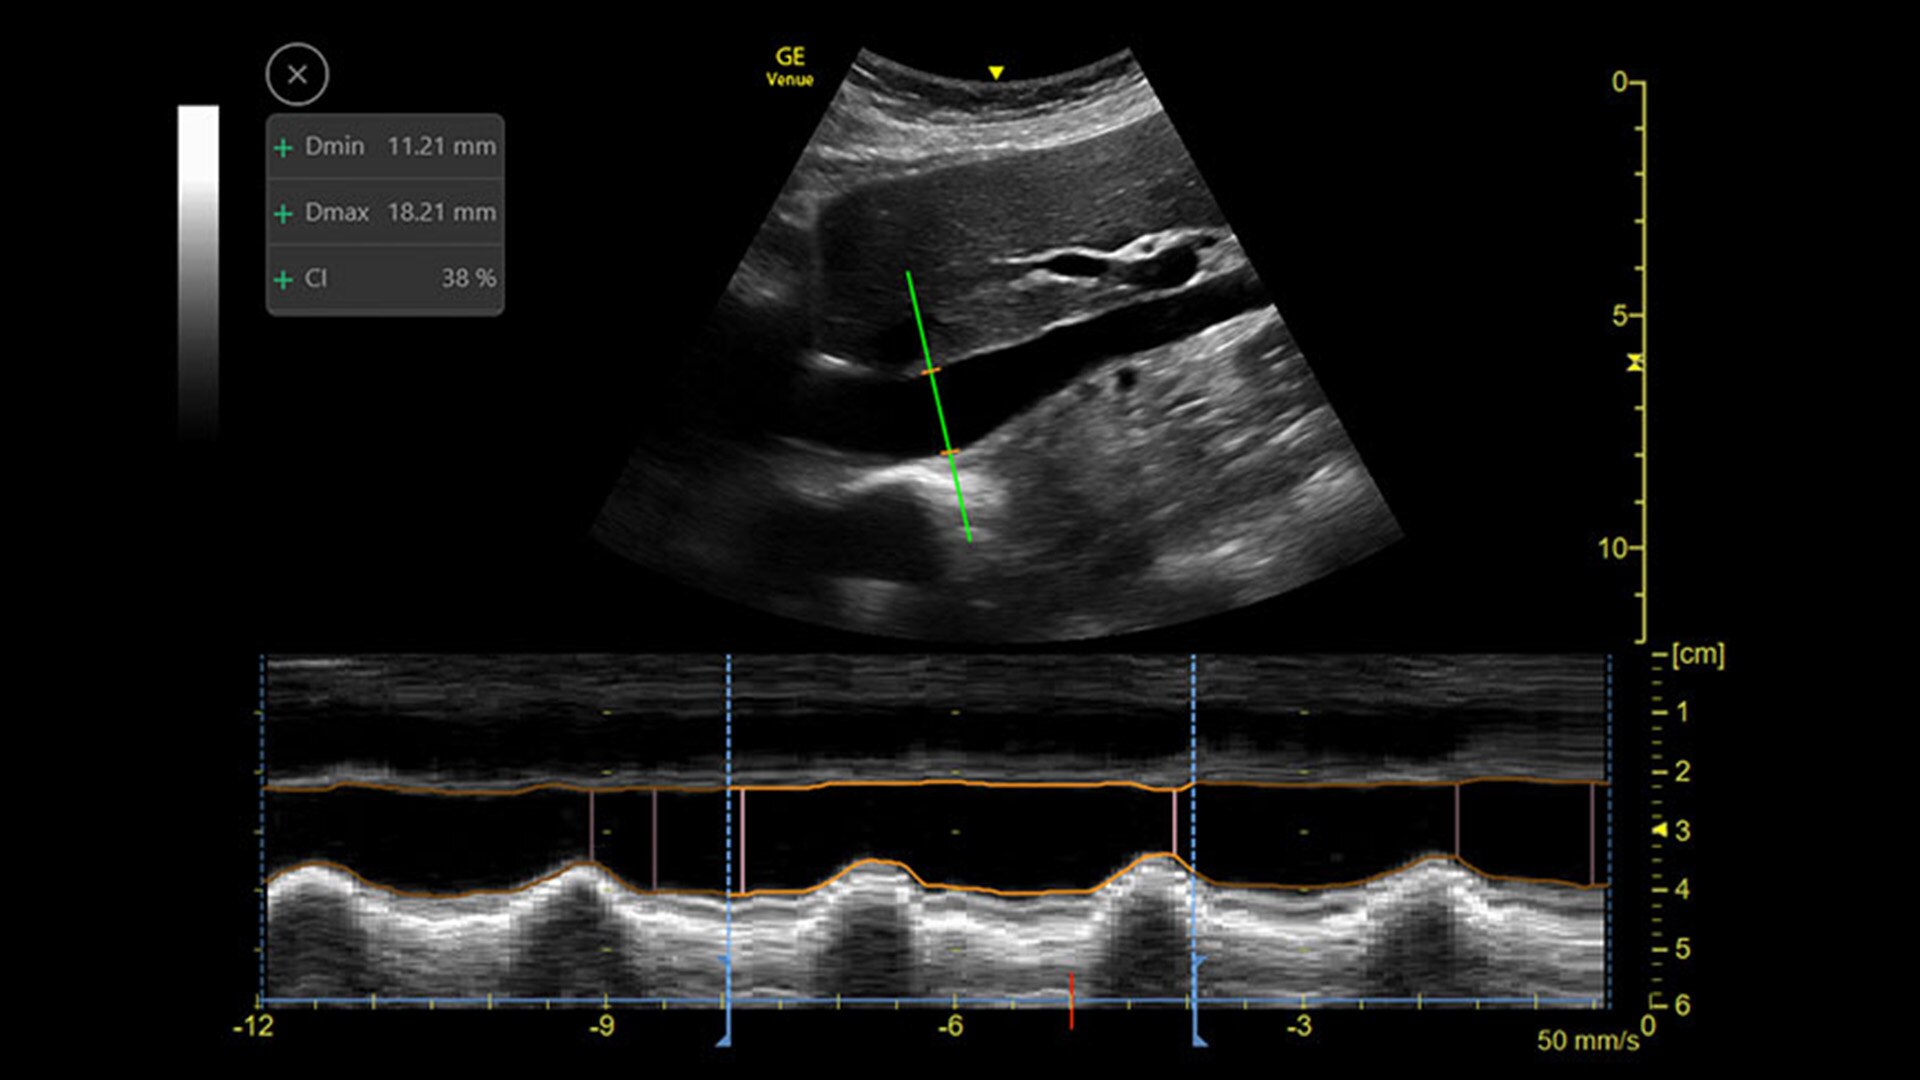

CATHETER TO VESSEL RATIO

Accurate catheter selection tool

Selecting the wrong sized catheter can lead to catheter related thrombosis.2 Catheter to Vessel Ratio is a measurement tool that supports clinicians in selecting the appropriate sized catheter based on vessel diameter.